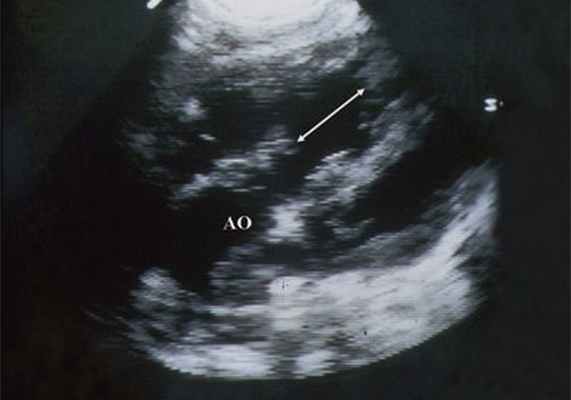

Рис. 6. Дефект межжелудочковой перегородки. Длинная ось сердца. Стрелками показан дефект межжелудочковой перегородки.